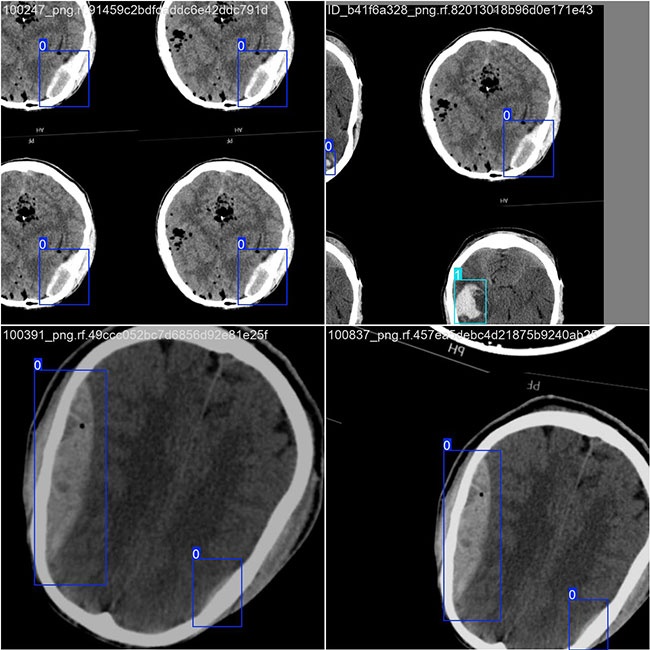

部分数据集图像如下图所示:

部分标注如下图所示:

在本研究中,我们采用了包含了颅内出血图像目标的数据集,并通过Labelimg标注工具对每张图像的目标边界框(Bounding Box)及其类别进行了标注。基于该数据集使用YOLOv8n模型进行了训练,并对模型在验证集上的性能表现进行了全面评估与对比分析。整个流程包括以下步骤:首先准备数据集;接着进行模型训练;最后进行模型评估。本研究主要关注的目标类别集中在颅内出血图像目标上。该数据集中总计包含42210张图像的具体分布情况如下:

训练集:包含29546张图像的数据集,默认情况下用于模型的学习与优化;验证集:拥有8442张图像的数据集,默认情况下主要用于评估模型对新数据的泛化能力,并防止过拟合;测试集:包含4222张图片的数据集合,在最终阶段用来评估机器学习算法的泛化性能